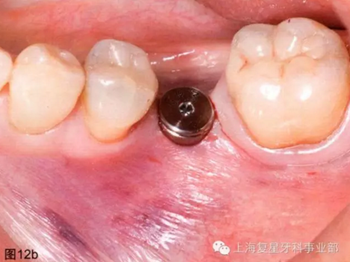

通過導(dǎo)板的引導(dǎo),以15prm,50Ncm旋入種植體。一旦種植體到達最后的深度(圖12a),去除種植手機和攜帶器,然后將一個愈合基臺(BioHorizons,直徑4.5毫米×長3毫米)擰在種植體上(圖12b)。軟組織打孔器取出的軟組織進行結(jié)締組織移植,然后放置在一個頰楔上獲得一定體積和厚度的角質(zhì)化軟組織(圖12c)。無需縫合。術(shù)后拍攝X片,對種植體的最終位置進行評估。

圖12b:已放入愈合基臺